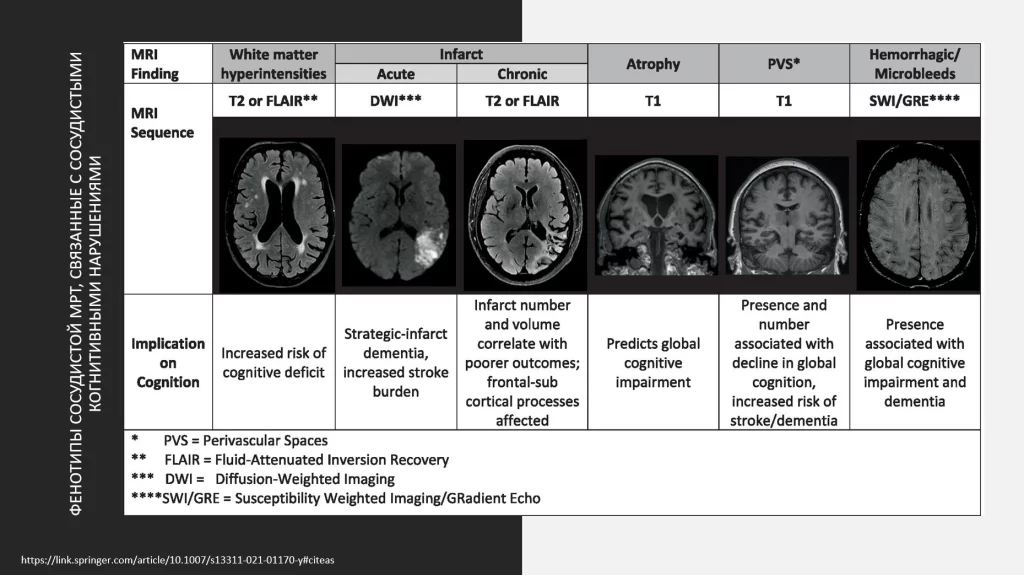

Есть очень четкие критерии по нейровизуализационным показателям, которые можно обнаружить у пациентов с сосудистыми, либо с нейродегенеративными нарушениями.

Выше представлены протоколы STRIVE, с которыми многие знакомы.

Они описывают фенотипы сосудистых нарушений, которые можно визуализировать по данным магнитно-резонансной томографии и, соответственно, решать вопрос, будут ли эти процессы протекать в разряде сосудистых патологий или нейродегенерации.